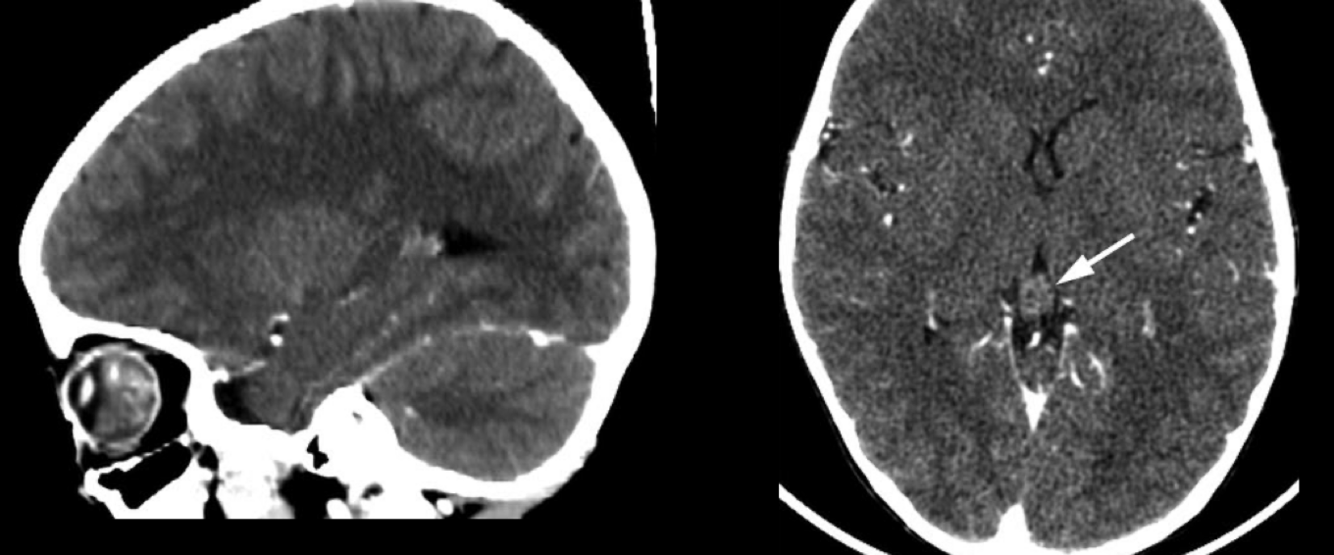

Hiperdensidad /intensidad

Fluido subretiniano

Retina triangulár

A

Desprendimiento retina en TC o rm